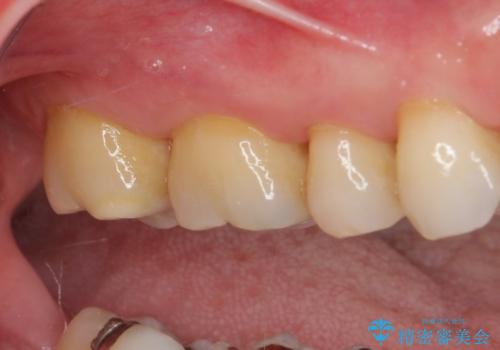

ゴールドインレーは銀歯のインレーやセラミックインレーと比べ、「技工操作の精度が高く、適合が著しく良い」というメリットがあります。特に上の奥歯は歯科医師の操作が行いにくいため、「適合の良さ」は再治療のリスクを防ぐ上でとても重要な要素となります。

上の奥歯は金属色が見えることもないため、審美的な問題は全くありません。

咬み心地はとても良好で、全く違和感がなく、患者様には大変満足していただきました。